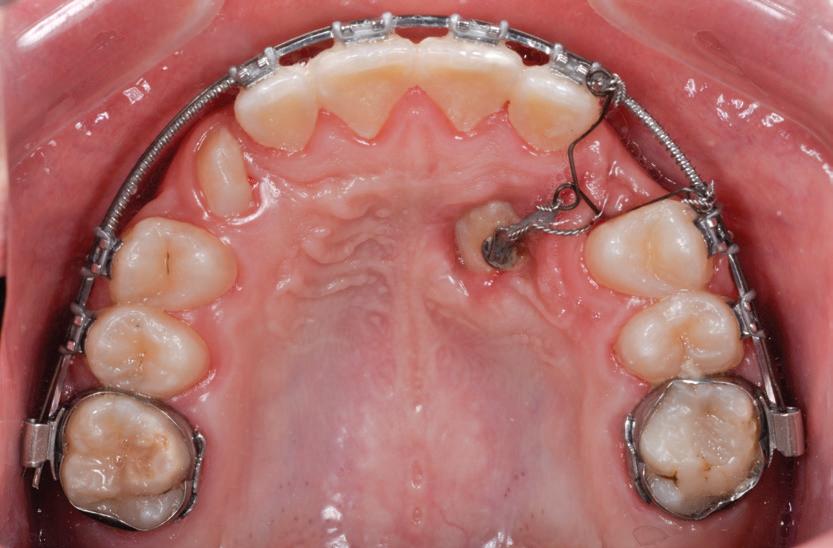

• Pacient cu restaurări deficitare pe dinți compromiși structural, tratamente endodontice eșuate, mobilitate avansată, pungi parodontale profunde, incisiv lateral absent congenital restaurat prin substituție canină inestetică, linie înaltă a zâmbetului. Rezolvarea? Colaborarea cu endodont, parodontolog, ortodont, protetician. Rezultatul? Succes clinic și satisfacția pacientului.

Pentru a ajuta clinicienii în determinarea tratamentului optim al unui canin maxilar inclus, figurile 1a, b, c prezintă arborele de decizie chirurgical / ortodontic.

Pentru tracționarea dinților impactați, este importantă utilizarea fie a unui arc de sârmă cu bază dreptunghiulară din oțel inoxidabil, fie o bară transpalatinală groasă, cu rigiditate adecvată. Acest lucru este esențial în special la caninii incluși palatinal. Evitarea utilizării arcurilor flexibile poate permite un control mai bun al efectelor adverse asupra dinților adiacenți în timpul tracțiunii. Se poate obține o ancorare suficientă în interiorul arcadei, prelucrând secvența până la arcurile 0,019 x 0,025 într-un slot de 0,022. Acest lucru previne deformarea arcurilor, deschiderea ocluziei din cauza tracțiunii, intruziunea dinților adiacenți și alte efecte adverse conexe. S-au utilizat diferite elemente externe, cum ar fi porțile batante, arcurile transpalatinale, extensoarele Hass, arcurile guad helix, expansoarele Hyrax și dispozitivele de ancorare temporară (temporary anchorage devices, TAD), ca aparate de ancorare alternative. În cazul unei bare transpalatinale, obiectivul este de a utiliza brațele de extensie în consolă pentru a tracționa caninul impactat în palat. Aceasta este urmată de tracțiunea caninului în poziția sa finală, utilizând arcuri de poziționare sau alte metode pentru a aduce dintele inclus pe arcada dentară (fig. 4, 5).